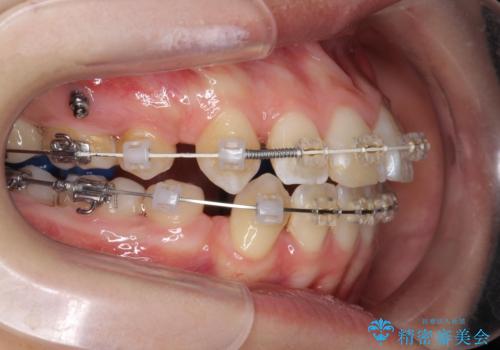

- 矯正装置

- ワイヤー矯正

前歯の角度を改善するために小臼歯4本の抜歯を行いワイヤー マルチブラケットを用いて、しっかりと前歯の角度を改善する治療計画としました。